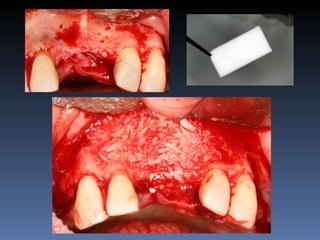

BOX 2

Silvia Maria Cardoso

Idade – 40 anos

Sexo – Feminino

Raça – Caucasiana

ASA – II

Data- 24-04-2012

Diagnóstico: Desdentada pré-maxila

Plano de tratamento:        Reabilitação com 2 blocos

“onlay” provenientes de Ilíaco fresco-congelado

(FFB); e posterior reabilitação protética fixa .

Leito nativo atrófico

Preparação e modelação dos blocos

Descorticalização do leito receptor

Fixação dos blocos “ onlay “

Mensuração pós fixação:

Pré - 1,0 mm

Pós – 5,5 mm

Pós-op 7 dias